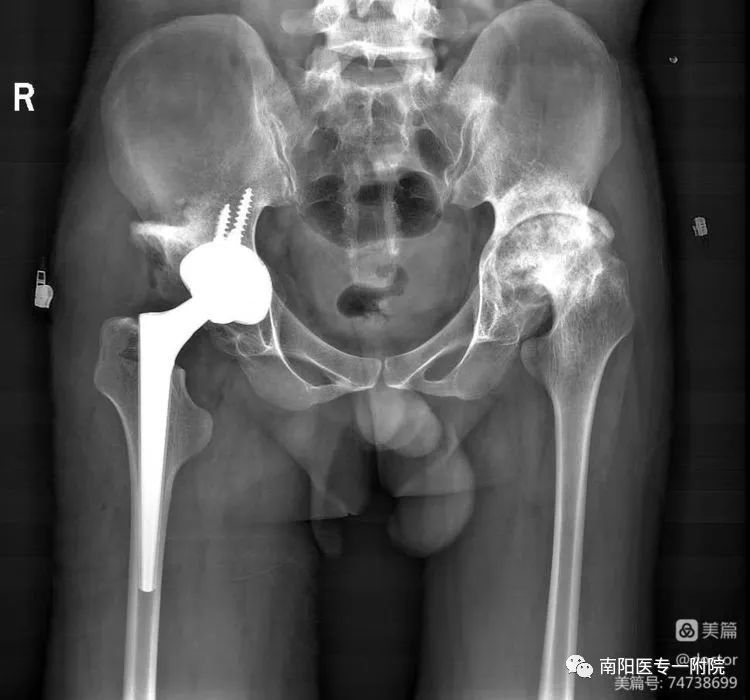

术后置换关节位置良好